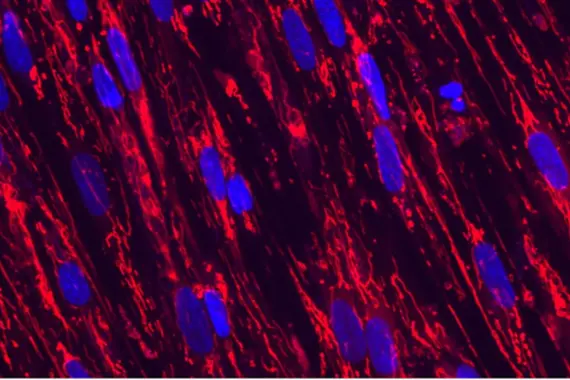

Multiplex immunofluorescence staining illustrating intradermal sheets of migrating stratified squamous epithelium and associated inflammatory response in Hidradenitis suppurativa.

Immunology

The Immunology group is developing transformative therapies, including small molecules and biotherapeutics, that target the root cause of disease by modulating the immune system to restore health.